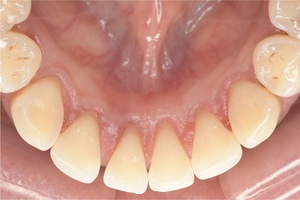

CASE 13

Before

After

基本情報

| 年齢・性別 | 31歳・男性 |

|---|---|

| 主訴 | 歯石をとりたい |

| 治療内容 | スケーリング |

| 治療期間 | 30分 |

| 治療費 | 1,500円(保険診療) |

| リスク・副作用 | 知覚過敏、歯肉退縮 |

| 治療方針 |

定期的なメインテナンスで歯石を除去していきます。 歯石が付くのを予防するため普段から歯間ブラシ、フロスを活用してセルフケアを行ってもらいます。 |